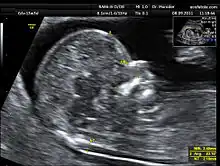

La translucencia nucal consiste en la medición de un espacio sonoluscente o econegativo situado en la zona posterior de la nuca del feto. El momento adecuado para realizar esta medición es la semana 12 aunque puede realizarse entre las semanas 11 y 14 del embarazo.

Para realizarse correctamente el calliper o cursor ecográfico se debe posicionar en las partes internas de los ecos que definen la sonoluscencia. La ecografía debe realizarse vía abdominal aunque pueden obtenerse las imágenes también vía vaginal.

Durante la medición debe medirse la Longitud Cráneo Caudal (LCC) o Longitud Céfalo Nalga (LCN), conocida en inglés como Crown Rump Length (CRL), para ajustar la edad gestacional. Todo ello permite que la medición de estos datos se añada de forma precisa a la valoración de dos hormonas placentarias en el suero materno (la PAPP-A o proteína A asociada al embarazo) y la Beta HCG (Gonadotropina Coriónica Humana), para determinar mediante un programa informático en el que se determinan las desviaciones de la normalidad o MoM, múltiplos de la mediana de los marcadores descritos y se calcula el llamado riesgo ajustado a partir del riesgo basal que depende de la edad materna.